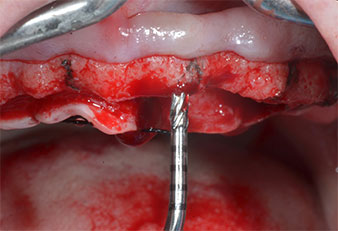

Ein flammenförmiges, diamantiertes piezochirurgisches Instrument (Piezomed I1) wurde verwendet, um die Implantatpositionen zu markieren und die Pilotpräparationen durchzuführen (Abb. 3). Dabei wurde darauf geachtet, eine Auf- und Abbewegung mit reduzierter Leistung, voller Spülung und niedrigem Druck (unter 300 g) anzuwenden. Als Nächstes wurde ein Pilotinstrument (Piezomed I2A/I2P) zur initialen Erweiterung der Implantatlager auf einen Durchmesser von 2 mm verwendet (Abb. 4), gefolgt von einem 3-mm-Instrument (Abb. 5).

Ultraschallmarkerinstrument Piezomed

Abb. 3: Die Präparation mit dem Ultraschallmarkerinstrument Piezomed I1 erfolgt mit einer Auf- und Abbewegung, parallel zur Längsachse des Arbeitsteils.